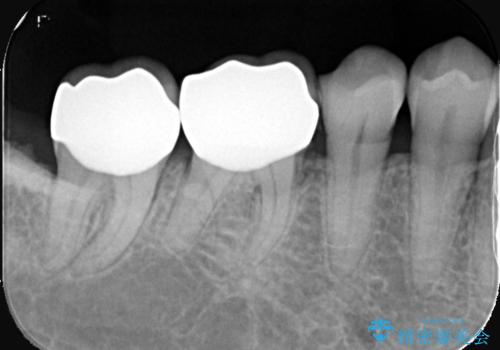

- 右下6番・7番の審美性と機能性を改善するため、セラミッククラウンでの治療を計画しました。1回目の来院時に古い被せ物や虫歯を丁寧に除去し、土台を整えた後に精密な型取りを行います。2回目の来院で仮のセラミッククラウンを装着して噛み合わせや適合性を確認し、最終調整を行います。3回目の来院時に完成したセラミッククラウンを装着し、最終調整を経て治療を完了します。

右下の奥歯にあった古い金属製のクラウンは、見た目の問題や歯ぐきの変色、さらには歯との境目に汚れが溜まりやすいなどの課題がありました。今回は審美的に優れ、生体親和性が高いセラミック素材を使用してクラウンを製作。色調は患者様の天然歯に合わせて調整を行い、自然で違和感のない仕上がりを目指しました。さらに精密な型取りと高度な技工技術を駆使することで、適合精度が非常に高いクラウンを提供しています。治療後は、見た目の美しさと噛み合わせの快適さが向上し、患者様には大変満足いただけました。